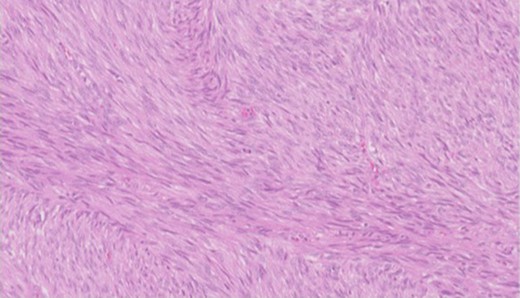

Pathology—GIST of spindle cell type (Figs 3 and 4), 90 mm in size, with complete local excision. Mitotic count—3 per 5 mm square. CD117 (Fig. 5) and DOG1 (Fig. 6) positive staining giving a prognostic group of moderate risk (Miettinen’s classification) of progressive disease. It is widely accepted that Interstitial Cells of Cajal (ICC) are pace maker cells of the gut and probable progenitor cells of GIST. Hyperplasia of ICC can be seen in cases with NF1, however, in this case this could not be shown in the background bowel (Fig. 7).

Higher power view showing the spindle appearance of tumour cells.